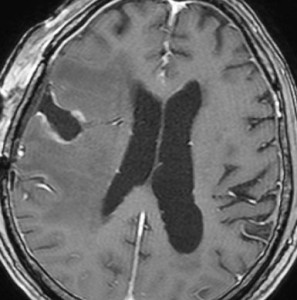

典型的な画像の変化

60代後半の患者さんで右前頭葉転移性脳腫瘍です。けいれん発作で発症しました。

定位放射線治療前

典型的な脳転移のMRIです。腫瘍は,リング状にガドリニウム増強され,内部が腫瘍壊死になっています。腫瘍周囲の脳浮腫がとても強いのが転移の特徴的画像所見(右側のT2強調画像)です。この転移巣に対して,35グレイ・5分割の定位放射線治療が加えられました。

定位放射線治療後

治療は奏功して,腫瘍は縮小して周囲の脳浮腫(右側)も軽減しています。

2年後 放射線壊死の進行

定位放射線治療後約2年,前の画像からはわずか3ヶ月後のMRIです。また右前頭葉の転移病巣が再発したかのように見えます。周囲の浮腫も広がって,左の片麻痺が悪化しました。しかし,ガドリニウム増強されて白くリング状に写る部分が不整形でまわりがギザギザしています。ステロイドを投与しましたが改善せずに悪化傾向を示しました。

手術後の脳浮腫の改善

手術で放射線壊死巣を摘出してから1月半後のMRIです。放射線壊死が摘出されて,脳浮腫もかなり改善しました。同時に右麻痺もよくなってきました。

この例では,アバスチンを投与するという選択肢もあったのですが,医療費が高額で患者さんが経済的に耐えられません。